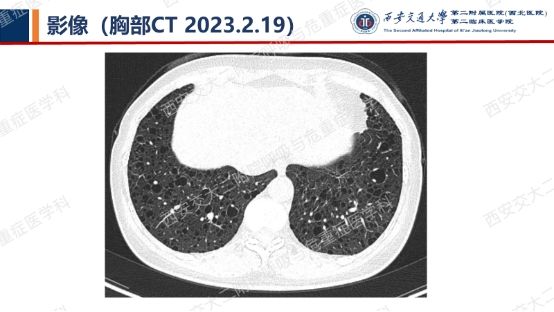

结合以上患者病史及胸部CT,第一诊断分别考虑???欲知答案,且看后期!!!